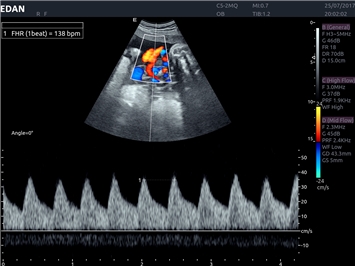

Высокочастотный импульсный допплер:

Да

Импульсно-волновой допплер: